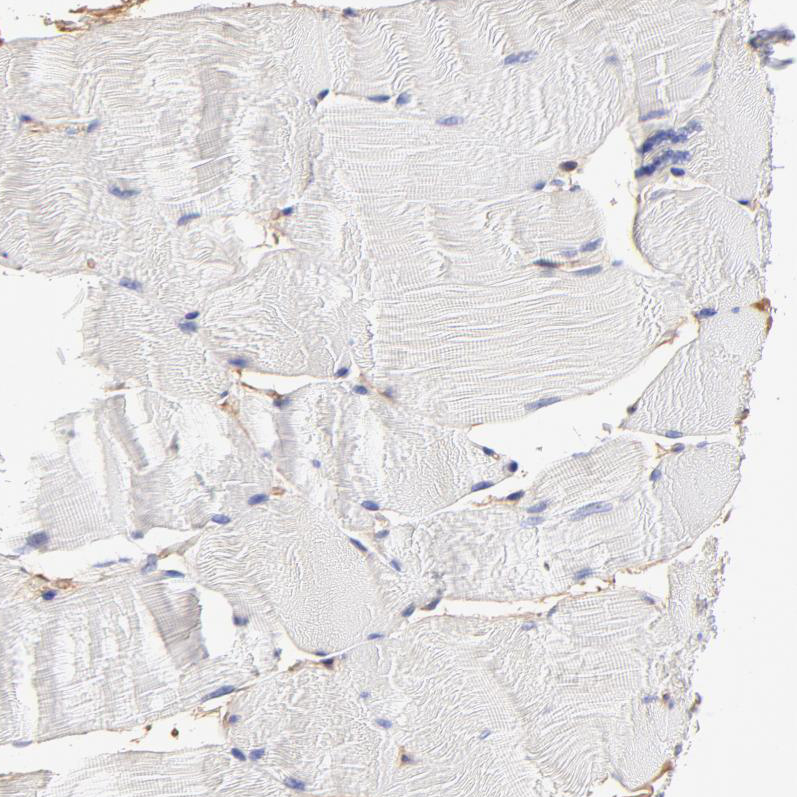

Immunohistochemistry analysis in human small intestine and skeletal muscle tissues using HPA003326 antibody. Corresponding CD2AP RNA-seq data are presented for the same tissues.